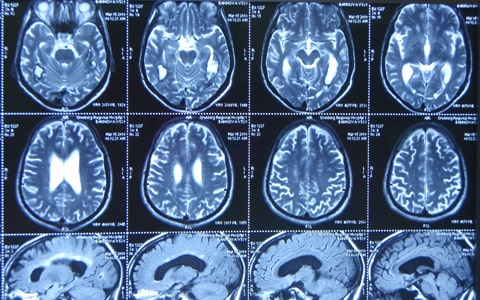

Что показывает МРТ головного мозга

В процессе исследования наш врач получает изображения, которые можно комбинировать, чтобы получить трёхмерные снимки в различных плоскостях и срезах. Далее он обнаруживает патологический очаг, измеряет его размеры и находит причину, спровоцировавшую появление болезни.

В итоге, пациенту устанавливается диагноз:

• Онкологическая опухоль доброкачественного либо злокачественного характера.

• Травма черепно-мозговой коробки.

• Синдром Альцгеймера.

• Остеохондроз шеи.

• Инфаркт, инсульт.

• Рассеянный склероз.

• Аномалия гипофиза или турецкого седла.

• Воспаление в тканях/сосудах мозга.

Это далеко не все диагнозы, устанавливаемые путём проведения томографического сканирования. Однако чем раньше вы обратитесь и пройдёте исследование, том больше шансов восстановить повреждённый участок мозга.